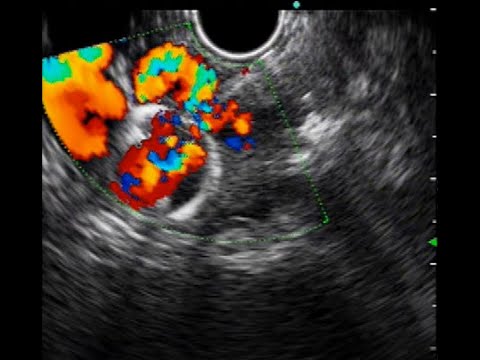

Hellow guys, Welcome to my website, and you are watching GASTRIC VARICES GLUE INJECTION. and this vIdeo is uploaded by Siddharth Javia at 2022-10-14T00:06:43-07:00. We are pramote this video only for entertainment and educational perpose only. So, I hop you like our website.